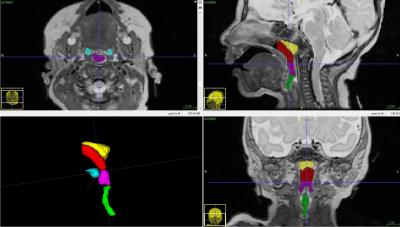

Las estructuras de la vÃa aérea de interés para esta investigación incluyen la nasofaringe (la parte superior de la faringe), la orofaringe (ubicada en la parte posterior de la boca detrás de la cavidad oral), la hipofaringe (la entrada al esófago), las adenoides (vegetaciones) y las amÃgdalas.

Se obtuvieron imágenes volumétricas en tres planos perpendiculares y un modelo tridimensional. “El volumen nasofarÃngeo de los recién nacidos a término fue de 495,6 mm, en comparación con 221,1 mm en los recién nacidos prematuros. El volumen orofarÃngeo de los recién nacidos a término fue de 313,6 mm, en comparación con 179,3 mm en los recién nacidos prematuros”, detallan los investigadores.